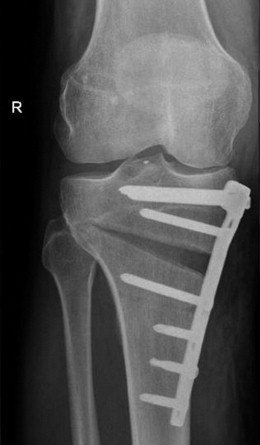

أولًا: اصلاح تقوس الساقين باستخدام الشرائح والمسامير

تُعد هذه الطريقة من أكثر جراحات تصحيح التقوس شيوعًا، وتناسب الحالات ذات الزوايا المتوسطة، بشرط عدم وجود خشونة شديدة بالمفصل.

يتم خلال الجراحة إجراء قطع عظمي دقيق في أعلى عظمة القصبة، ثم تصحيح زاوية التقوس وتثبيت العظم باستخدام شريحة ومسامير طبية عالية الجودة.

تساعد هذه الجراحة على:

- استقامة الساق

- إعادة توزيع الأحمال على مفصل الركبة

- تقليل الألم

- إبطاء أو منع تطور خشونة الركبة

- زيادة طفيفة في طول الساق

عادة لا يحتاج المريض إلى إزالة الشرائح والمسامير، إلا إذا رغب في ذلك بعد اكتمال الالتئام.

تكلفة عملية تقوس الساقين باستخدام الشرائح والمسامير تتأثر بنوع الشرائح، ومدى الحاجة إلى ترقيع عظمي، لكنها تظل خيارًا اقتصاديًا فعّالًا على المدى الطويل مقارنة بتكاليف علاج الخشونة لاحقًا.